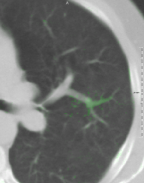

MIND: The Modality Independent Neighborhood Descriptor (MIND) was introduced by Heinrich et al. [2012] in order to register multi-modal images. In this local self-similarity metric, a patch is considered to compare intensities between fixed and moving images. Finally, the sum of absolute differences between the MIND vector of IFsubscript𝐼𝐹I_{F} and that of IM(𝑻b)subscript𝐼𝑀superscript𝑻bI_{M}(\bm{T}^{\mathrm{b}}) is computed. We calculate MIND with a sparse patch including 82 voxels inside a [7×7×3]delimited-[]773[7\times 7\times 3] box, which is approximately physically isotropic for the data used in the experiments (see Fig. 4).

Refer to caption

(a) 2D projection

(b) 3D view

Figure 4: MIND search region. (a) The green cell indicates the center and darker blue cells indicate more accumulated cells in the projection view.